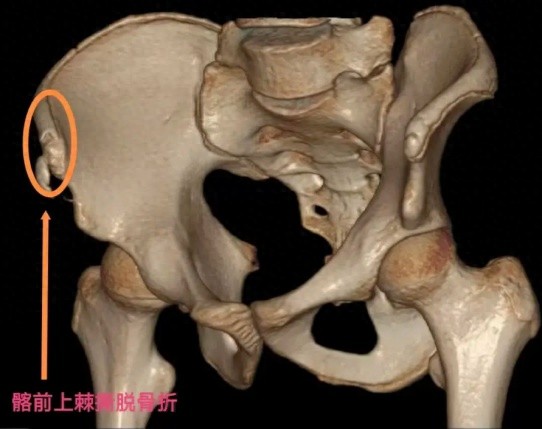

家长赶紧带他来到浙中医大二院(省新华医院)骨伤科,接诊的崔龙慷医生安排他拍了骨盆X光片。结果让大家都吃了一惊:右侧髂前上棘撕脱性骨折,一块小骨头被肌肉从骨盆上硬生生"拽"了下来。

3D图片示意

髂前上棘撕脱骨折X片